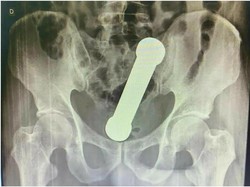

Barbel Nyangkut dalam Dubur Pria Umur 50 Tahun, Kok Bisa?

Seorang pria berusia 50 tahun mengeluhkan kondisi medis yang tak biasa. Pasalnya, ia mengeluh ada barbel yang menyangkut di dalam duburnya. Lah kok bisa?